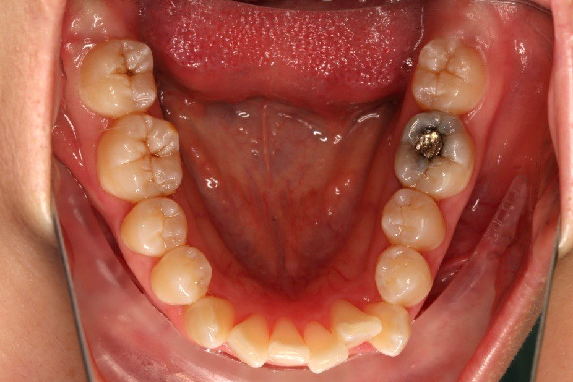

• 磨牙,尖牙I类关系,中线齐

• 上下牙列中度拥挤

• 上下前牙唇倾

IntraoralExamination(2016-08.31,Wu)

2018.11.14  术后磨牙尖牙I类关系,中线齐,覆合,覆盖正常

牙根基本平行,未见牙根吸收